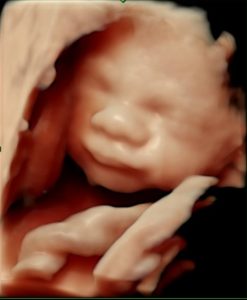

Uge 29: Fosterets udvikling

Fosteret er omkring 38–40 cm langt og vejer cirka 1.300–1.400 gram.